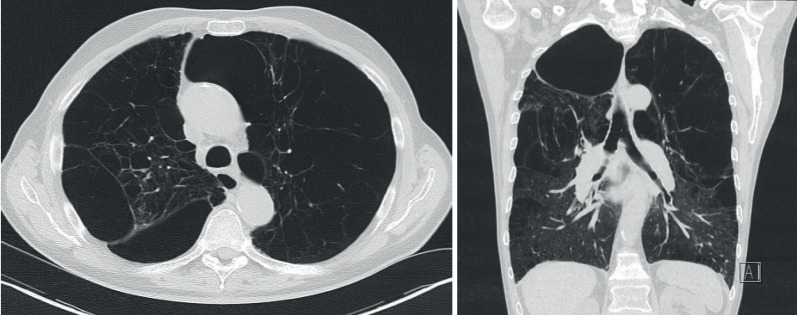

体积缩小是一种疾病修饰治疗,旨在通过去除严重受损和过度膨胀的肺实质,重塑患病肺,使其达到更正常的肺总容量。在精心挑选的患者中,它是一种有效的治疗策略,可以改善运动耐量、肺功能、生活质量和生存率。最广泛的减容策略是电视胸腔镜手术或支气管镜肺减容。决定哪种方法更适合特定的患者是至关重要的,因为这关系到手术的结果。计算机断层扫描上的肺气肿分布、有无侧支通气、患者肺功能检查、其他合并症史和既往干预等因素都可能影响手术的选择。这是至关重要的,这个决定是由一个多学科的专家团队做出的,以获得最好的结果和更少的并发症。

Volume reduction is a disease-modifying treatment that aims to reshape the diseased lung towards a more normal total lung capacity by removing severely damaged and overinflated lung parenchyma. It is an effective therapeutic strategy in well-selected patients, resulting in improvements in exercise tolerance, lung function, quality of life and survival. The most widespread strategies for volume reduction are either video-assisted thoracoscopic surgery or bronchoscopic lung volume reduction. It is crucial to decide which approach would be more suitable for specific patients, as this is related to the outcome of the procedure. Factors like emphysema distribution on computed tomography, the presence or absence of collateral ventilation, the patient's pulmonary function tests, a history of other comorbidities and previous interventions might all influence the choice of procedure. It is crucial that this decision is taken by a multidisciplinary expert team to have the best outcome and fewer complications.